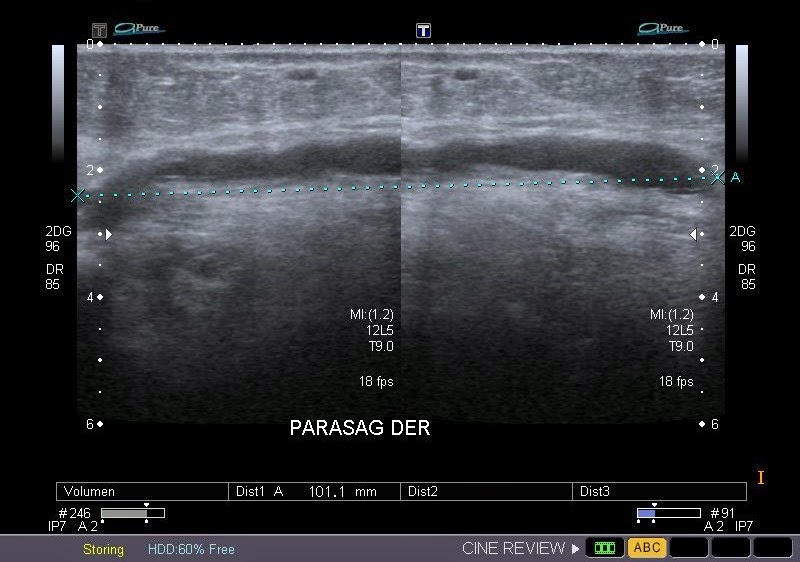

INGRESO

Paciente con antecedente de ALIF (Fusión lumbar intersomática anterior) 360 grados L5-S1 hace siete meses, quién presenta herida de abordaje anterior con dehiscencia de sutura, con cierre por segunda intención, quien consulta por cuadro clínico de dos días de secreción purulenta en herida quirúrgica, niega fiebre, niega otras sintomatología, refiere episodios previos similares.

EVOLUCIÓN

Paciente en POP de ALIF L5-S1 quien presento dehiscencia de la herida abdominal con ISO superficial ya tratada, sin embargo persiste con dehiscencia y desde ayer con supuración asociado a fiebre subjetiva. Se realiza eco abdominal con colección en pared sugestiva de absceso, elevación de RFA por lo cual se considera se debe hospitalizar para manejo antibiótico, drenaje de la colección, manejo médico y vigilancia neurológica.

- ¿Hallazgos Escanografia?